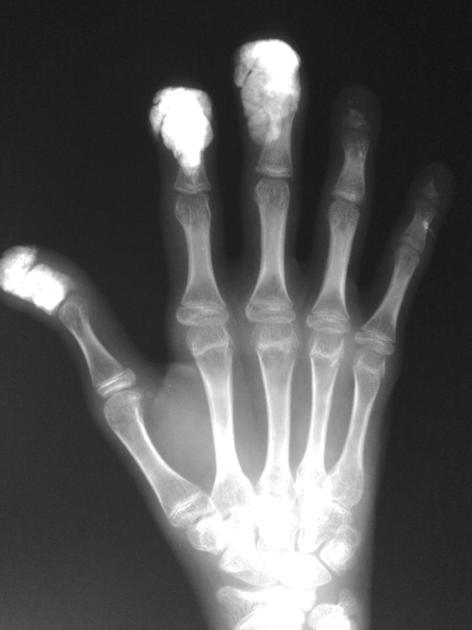

- Kožní projevy – oboustranné symetrické ztluštění kůže, které začíná distálně a typicky postupuje proximálním směrem. U některých jedinců je projevuje ztmavnutí kůže bez anamnézy slunění, u jedinců tmavé pleti spíše jako vitiligo, které šetří perifolikulární oblasti a dává kůži obraz „soli a pepře„, nejvíce v oblasti hlavy, šíje a hrudníku. Postižení kůže vede i ke ztrátě ochlupení, snížení pocení a odlupování kůže se svěděním. Flekční kontraktury mohou vést ke svalové atrofii. U jedinců s rozvinutou SSc se může objevit typický „mauskopf“ s vypnutou kůží obličeje, hypomimií, periorálním rýhováním a mikrostomií, která může zhoršovat zubní hygienu. Dále jsou patrny dilatované kožní kapiláry (teleangiektázie) obličeje a rukou, které často korelující se závažností mikrovaskulárního postižení. Poškození kožní mikrocirkulace vede k chronickým ulceracím (zejména na polštářcích prstů nebo kostěných prominencích, např. loktech a kotnících), které se obtížně hojí a zanechávají typické jizvy („digital pits„) až akrální osteolýzu. U pacientů s dlouhodobou lc-SSc a pozitivitou protilátek proti centromerám dochází ke kalcifikacím kůže a měkkých tkání s precipitací krystalů hydroxyapatitu do tkání poškozených zánětem nebo hypoxií, které lze zobrazit na RTG nebo CT.

- Muskuloskeletální postižení – běžné jsou bolesti kloubů s postupným postižením hybnosti, dále myalgie se svalovou slabostí a vznikem krepitací nad šlachami. CAVE Přítomnost šlachových krepitací znamená zvýšené riziko renálních a srdečních komplikací a zkrácené přežívání. Mikroangiopatie vede k ischemii a osteolýze akrálních částí těla.